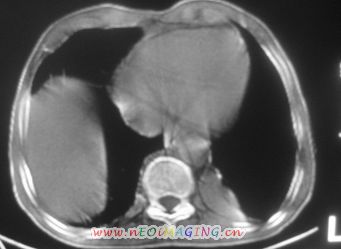

以下是引用卜一在2007-10-7 9:38:00的发言:[br]左下肺胸膜下团片影,内见含气支气管像,临近胸膜未见增厚。多考虑:1 左下肺炎症,建议消炎后复查!2 不除外肺隔离症合并感染!